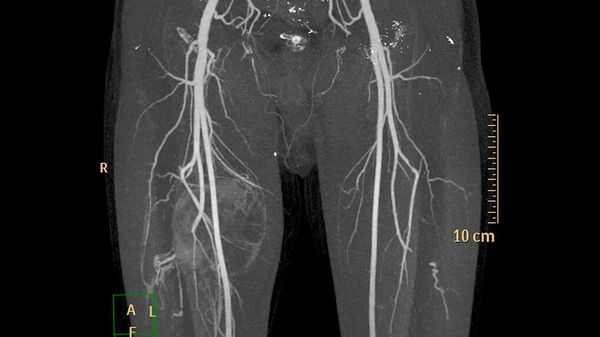

- ультразвуковое исследование (УЗИ) и магнитно-резонансную томографию (МРТ) для первоначальной диагностики [12] ;

- компьютерную томографию (КТ) для оценки костной ткани;

- рентгеноконтрастную флебографию (введение в просвет вен рентгеноконтрастного вещества) для планирования лечения [7] .